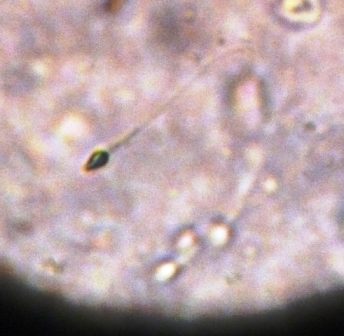

Researchers from the National Institute of Child Health and Human Development have developed a topical gel designed for men that has the potential to slow down and prevent the production of sperm.

The basis of the contraceptive gel is hormones progestin and testosterone. The progestin works to stop the man’s testes from producing enough testosterone to produce sperm. The added testosterone is then used as an alternative way to acquire the hormone without producing a hormonal imbalance.

Theoretically, if applied according to researcher’s recommendations, the contraceptive gel should help suppress sperm levels for up to 72 hours.

A previous gel trial conducted by the National Institute in 2012 was able to successfully reduce the male’s sperm levels by 89 percent with minimal side effects.